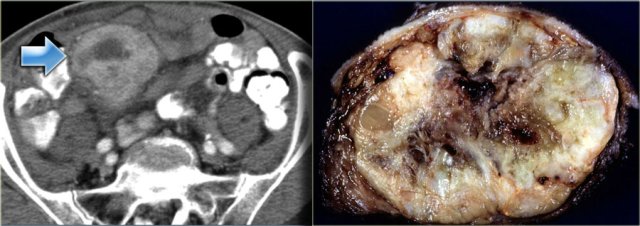

The case on the left is also a lymphangioma.

Notice that CT does not always appreciate the septations, although the specimen clearly shows multiple septations.

Ultrasound or MR depict these septations better than CT.